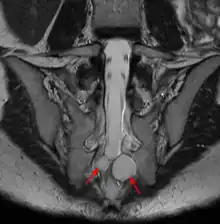

![]() | |

| MRI image showing a Tarlov cyst | |

Tarlov cysts are most commonly located in the S1 to S4/S5 region of the spinal canal, but can be found along any region of the spine. They usually form on the extradural components of sacrococcygeal nerve roots at the junction of dorsal root ganglion and posterior nerve roots and arise between the endoneurium and perineurium.[10] Occasionally, these cysts are observed in the lumbar and thoracic spine.[7] However, these cysts most commonly arise at the S2 or S3 junction of the dorsal nerve root ganglion.[11][12] The cysts are often multiple, extending around the circumference of the nerve, and can enlarge over time to compress neighboring nerve roots, to cause bone erosion.[13] The cysts may be found anterior to the sacral area and have been known to extend into the abdominal cavity. These cysts, though rare, can be found to grow large - over 3–4 centimetres (1.2–1.6 in) in size, often causing severe abdominal pain from compression on the cyst itself as well as adjoining nerves.

MRI, or Magnetic Resonance Imaging, is considered the imaging study of choice in identifying Tarlov cysts. MRI provides better resolution of tissue density, absence of bone interference, multiplanar capabilities, and is noninvasive. Plain films may show bony erosion of the spinal canal or of the sacral foramina. On MRI pictures, the signal is the same as the CSF one.